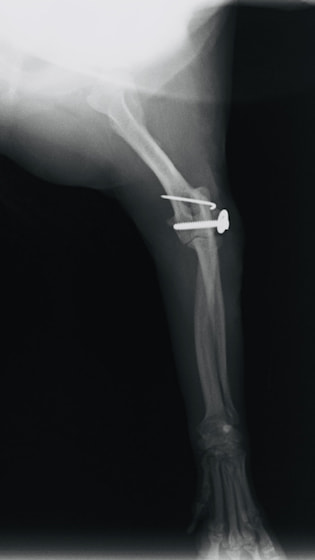

症例3:キルシュナーワイヤーのピンニングによる整復

ペルシャ猫 11ヶ月齢 雄

他院にて左大腿骨遠位の成長板骨折(salter-harrisⅠ型)が認められており、治療相談を目的として来院。当院にて、キルシュナーワイヤーを用いたピンニングにより骨折部位の整復を行いました。術後の経過は良好で、現在も経過観察中です。

術前レントゲン

術後レントゲン

Arthrex社のターゲティングデバイスを用いてピンニングの位置を調整することで、確実な固定を行っています。当院ではこの手術器具以外にも、人の手術にも使用される様々な器具を導入し、手術精度を高め、また医療メーカーと新しい器具の開発、試作にも取り組んでおります。